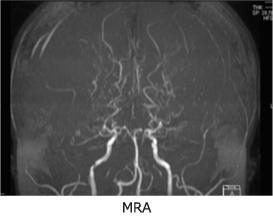

特定疾患のため定められた診断基準があります。以前は脳血管撮影が必須でしたが、現在ではMRI・MRAで診断可能です。ウィリス動脈輪の狭窄・閉塞ともやもや血管が認められ、診断基準を満たしていれば難病申請が可能です。医療費公的負担制度を利用できます。

MRI・MRA、3D-CTA(造影CT脳血管検査)検査で血管形態の精密検査を行います。また、脳血流検査で脳血流動態を検討します。ここまでは外来で日帰り検査です。この結果、血行再建手術が必要と判断された場合には、入院して行う脳血管造影検査(カテーテル検査)を行い、さらに詳細に血管の状態を調べます。